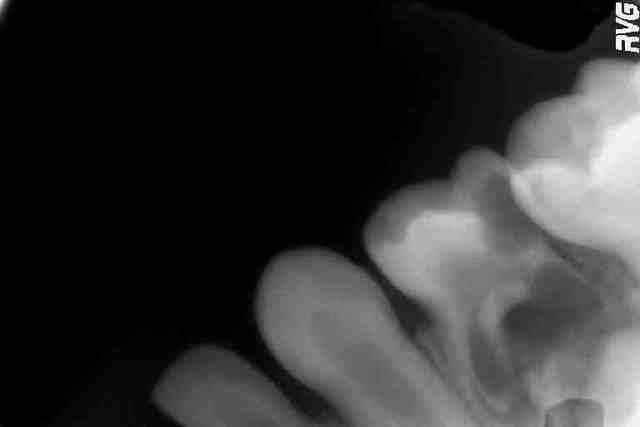

Ca peut très bien se passer. Sur la radio jointe, la dent de la petite Sandra, 4 ans, a eu besoin qu'on l "aide à tomber" plus tôt, c'était bouclé en 20 minutes et au rdv suivant Sandra m'avait fait un joli dessin.